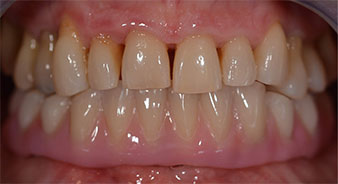

The 64-year-old patient presented with residual dentition of teeth 38, 33 and 43 and a clasp denture in the mandible (Fig. 1 and 2).

residual dentition

Fig. 2